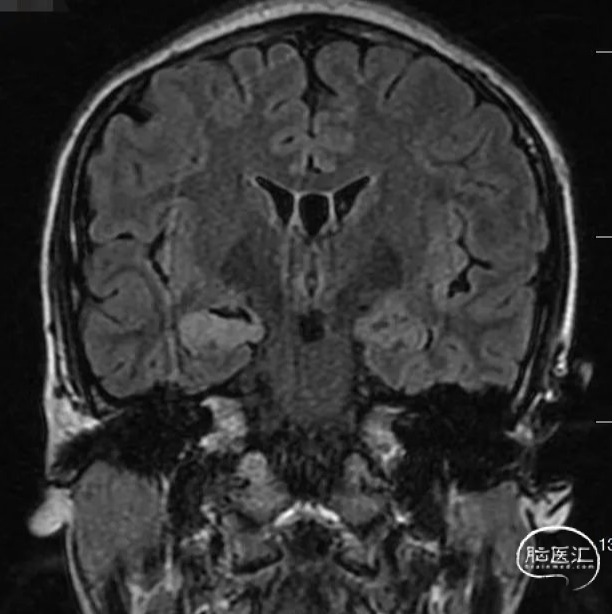

头颅MRI

头颅MR:双侧海马及杏仁核,双侧岛叶,左侧颞叶,双侧扣带回异常信号影。